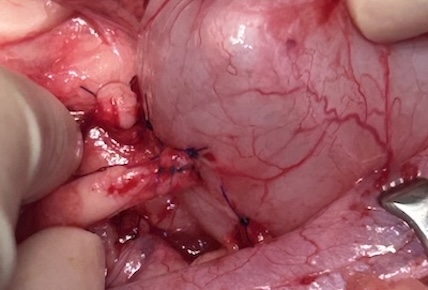

以下、術中の写真です(閲覧注意)

右側の腎臓は比較的尿管が拡張していたのと、拡張部位から膀胱までのテンションに余裕があったため、結石摘出後、摘出部から近位尿管を膀胱に吻合しました。 左の腎臓は皮質の菲薄化が重度であるため機能回復は乏しいと考え、尿管を切開して摘出・縫合するのみとしました。

右尿管からは1.0mm、左尿管からは2.5mm程度の結石をそれぞれ摘出しました。

左右の腎臓には術後の尿の迂回路として腎瘻チューブの設置を行いました。